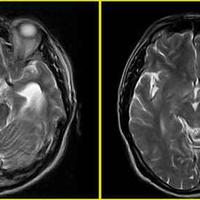

发现颅内占位5天,脑膜瘤?

发现颅内占位5天,脑膜瘤?...

由 medjpg 发表于 2026-03-24 22:32